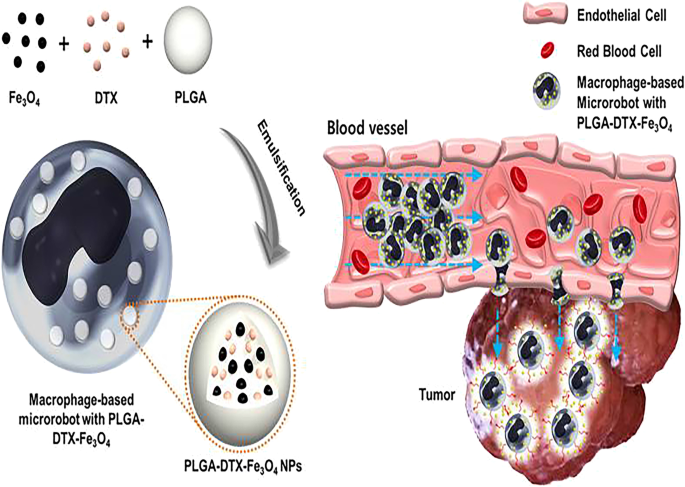

Иллюстрации из Cell Discovery: Удивительный мир науки через фотографии

Раздел: Фотоэссе